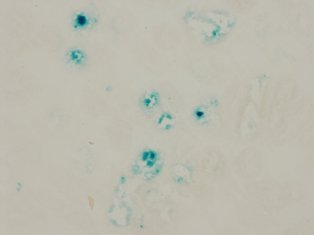

・Elucidation of the role of cellular senescence in kidney diseaseIn diabetes and hypertension, as the disease progresses, blue stained tubules appear in the kidneys as shown in the picture. These cells are considered as "senescent cells" and it is known that such cells appear not only in aging but also in the diseases mentioned above. So what are the function of these senescent cells? Are these blue stained cells behave like normal cell? Or does the presence of these cells have adverse effects in the kidney? The answer is, “we are not sure yet”. Our goal is to figure out whether these "aging cells" are playing a good role or a bad role or not doing anything at all.